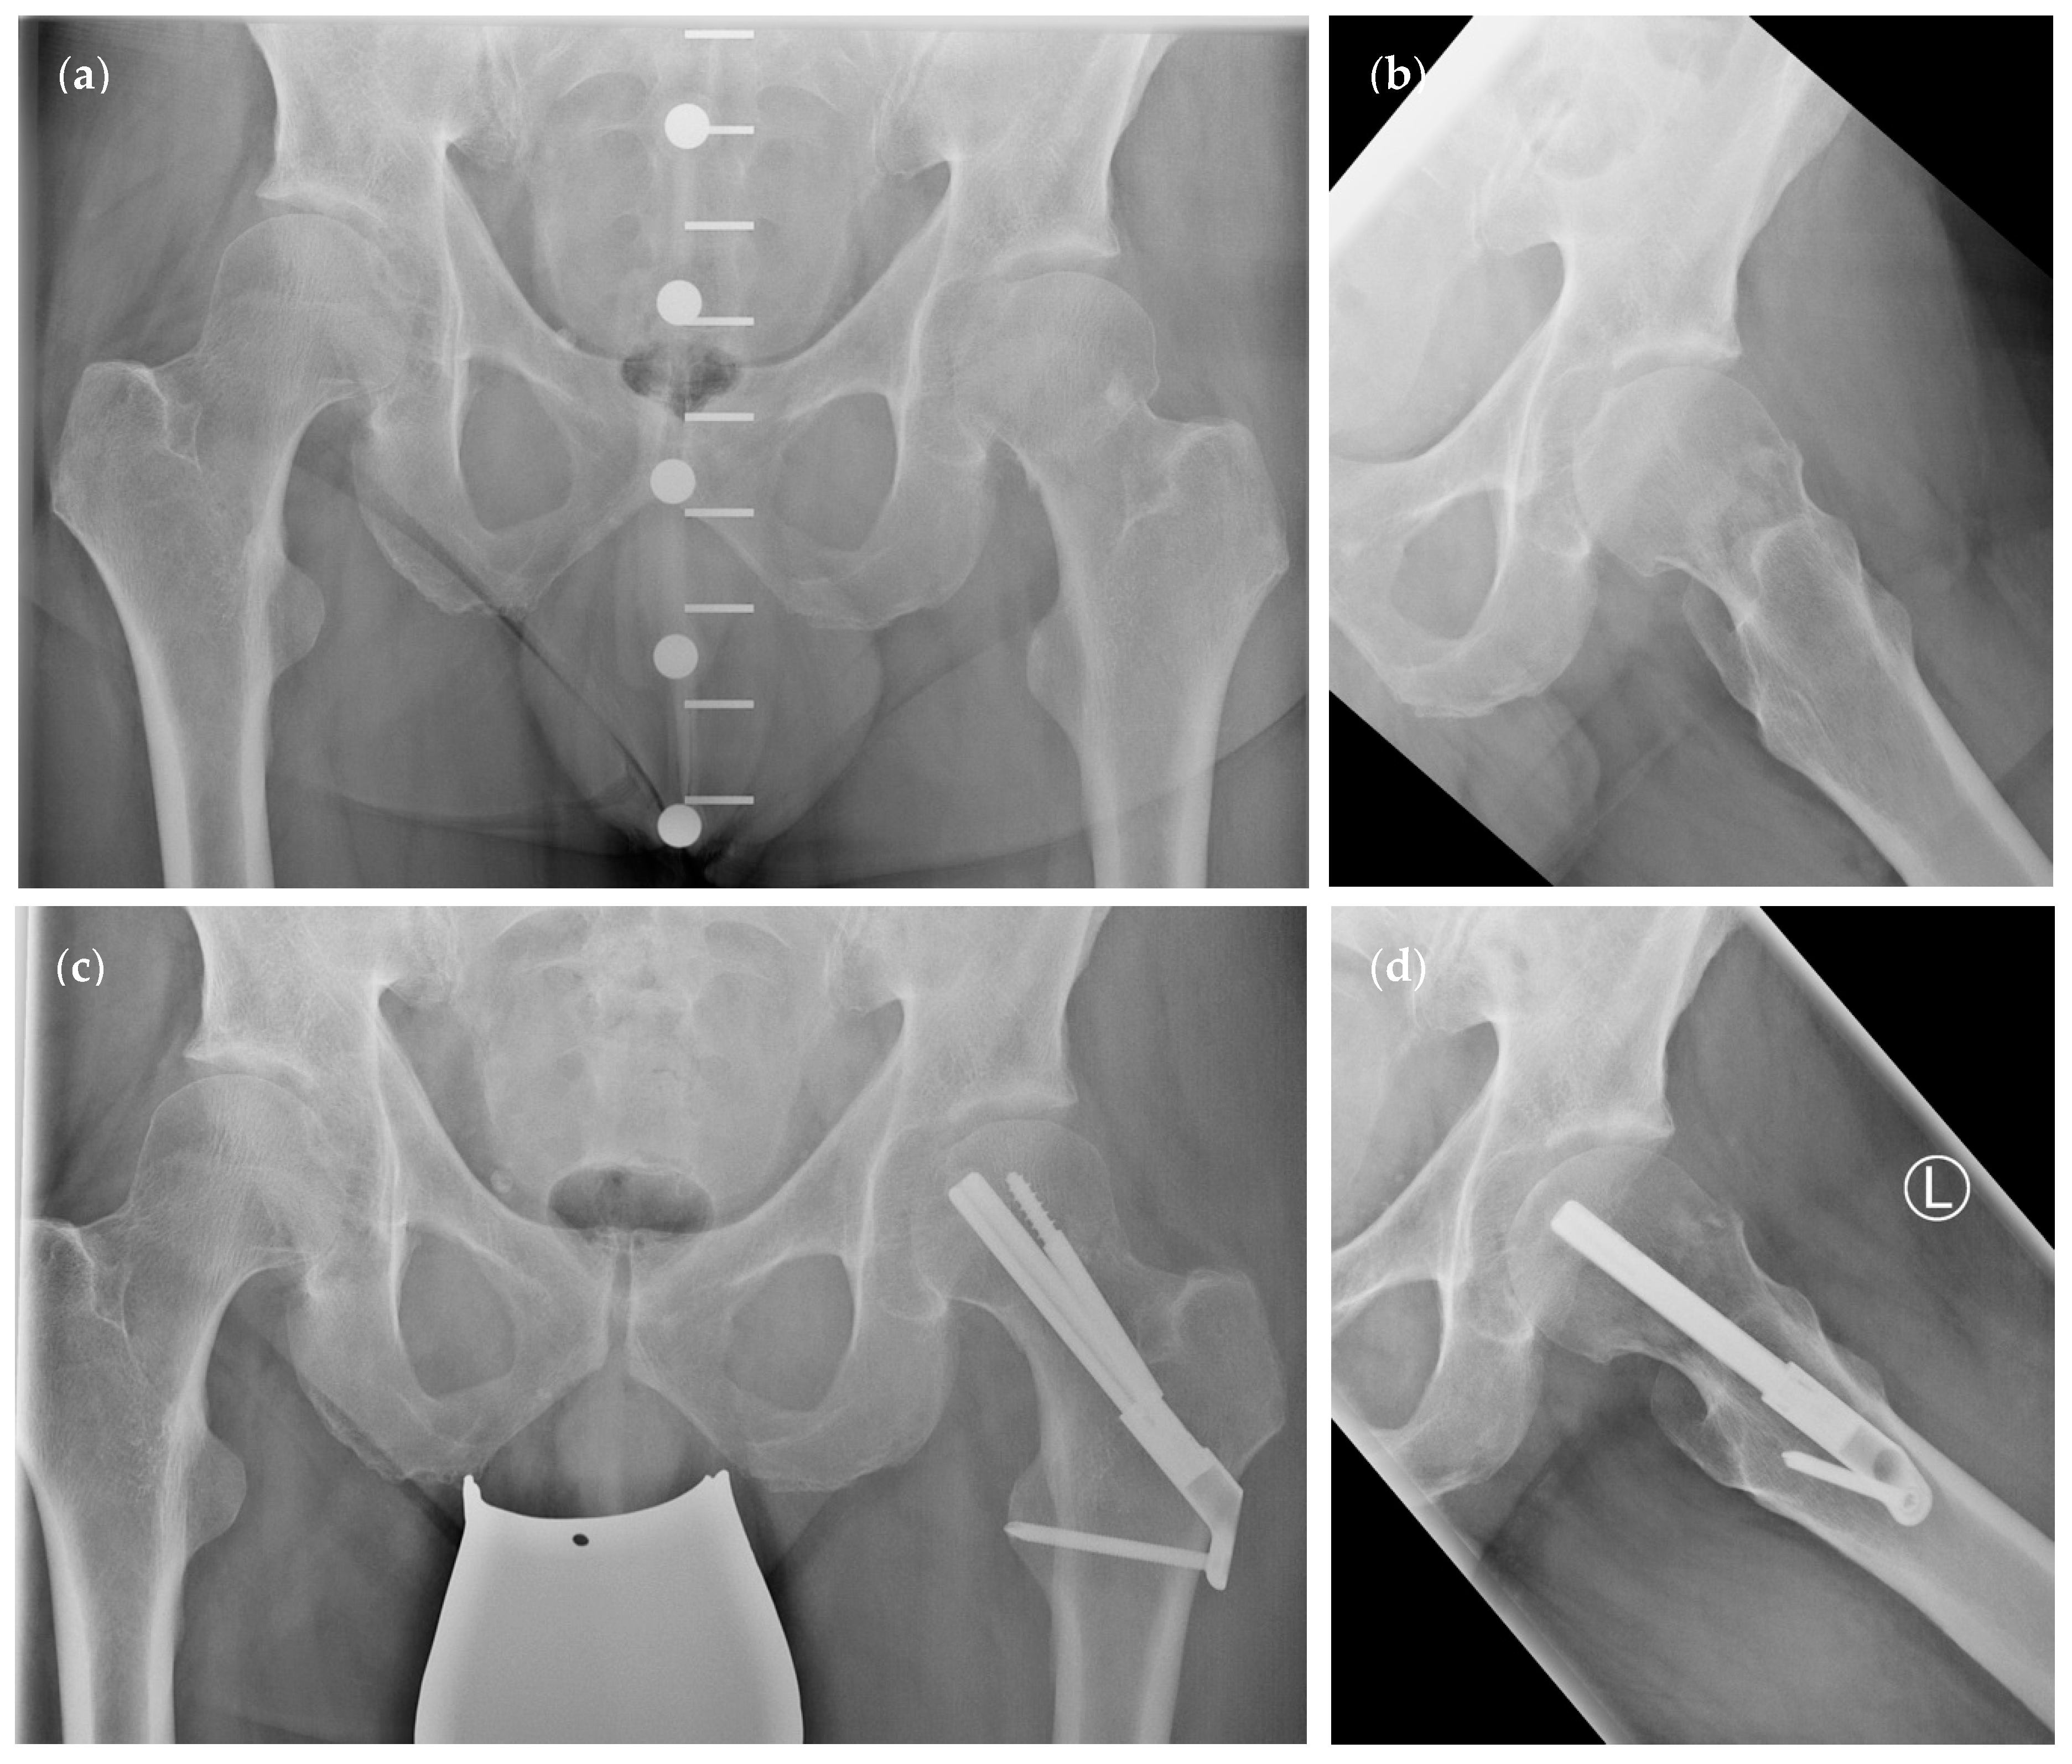

| Preoperative Pauwels angle (°) | 50.93 ± 14.07 | 47.66 ± 14.44 | p = 0.41 | |

| (95% CI 44.15–57.71) | (95% CI 38.49–56.83) | |||

| Postoperative Pauwels angle (°) | 46.74 ± 7.71 | 43.34 ± 7.93 | p = 0.22 | |

| (95% CI 43.03–50.46) | (95% CI 38.3–48.38) | |||

| Preoperative CCD angle (°) | 129.5 ± 16.21 | 130.8 ± 13.25 | p = 0.8 | |

| (95% CI 121.7–137.3) | (95% CI 122.4–139.2) | |||

| Postoperative CCD angle (°) | 135.9 ± 7.27 | 136 ± 5.24 | p = 0.85 | |

| (95% CI 132.4–139.4) | (95% CI 132.7–139.4) | |||

| Pauwels classification | Type I (% of group) | 1 (5.26%) | 1 (8.33%) | p = 0.72 * |

| Type II (% of group) | 10 (52.63%) | 7 (58.33%) | ||

| Type III (% of group) | 8 (42.11%) | 4 (33.33%) | ||

| Garden classification | Type I (% of group) | 2 (10.53%) | 1 (8.33%) | p = 0.45 ** |

| Type II (% of group) | 9 (47.37%) | 8 (66.67%) | ||

| Type III (% of group) | 4 (21.05%) | 2 (16.67%) | ||

| Type IV (% of group) | 4 (21.05%) | 1 (8.33%) | ||